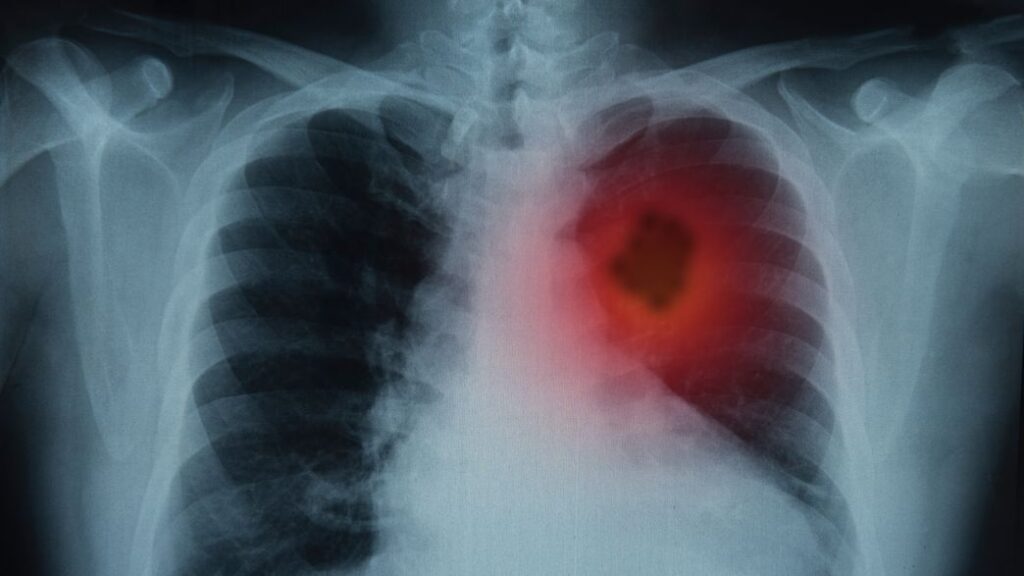

1. Tobacco Use

Perhaps the most notorious of cancer’s perpetrators is tobacco use. The ingestion of tobacco in any form, whether through smoking, chewing, or secondhand exposure, significantly increases the likelihood of developing various cancers, particularly lung cancer. The myriad of carcinogens within tobacco smoke incites mutations in DNA, paving the way for cancerous cells to proliferate. Additionally, tobacco-related cancers encompass throat, mouth, pancreas, and bladder, underscoring its insidious reach.

7. Radiation Exposure

Radiation is a widely known risk factor, but the nuances often go unnoticed. Both ionizing radiation, such as that from X-rays and radon gas, and non-ionizing radiation, from ultraviolet (UV) light, can elevate cancer risk. UV exposure is particularly notorious for skin cancers, including melanoma, while radon exposure is a significant concern in certain geographical regions. Implementing protective measures and awareness can be lifesaving in many contexts.